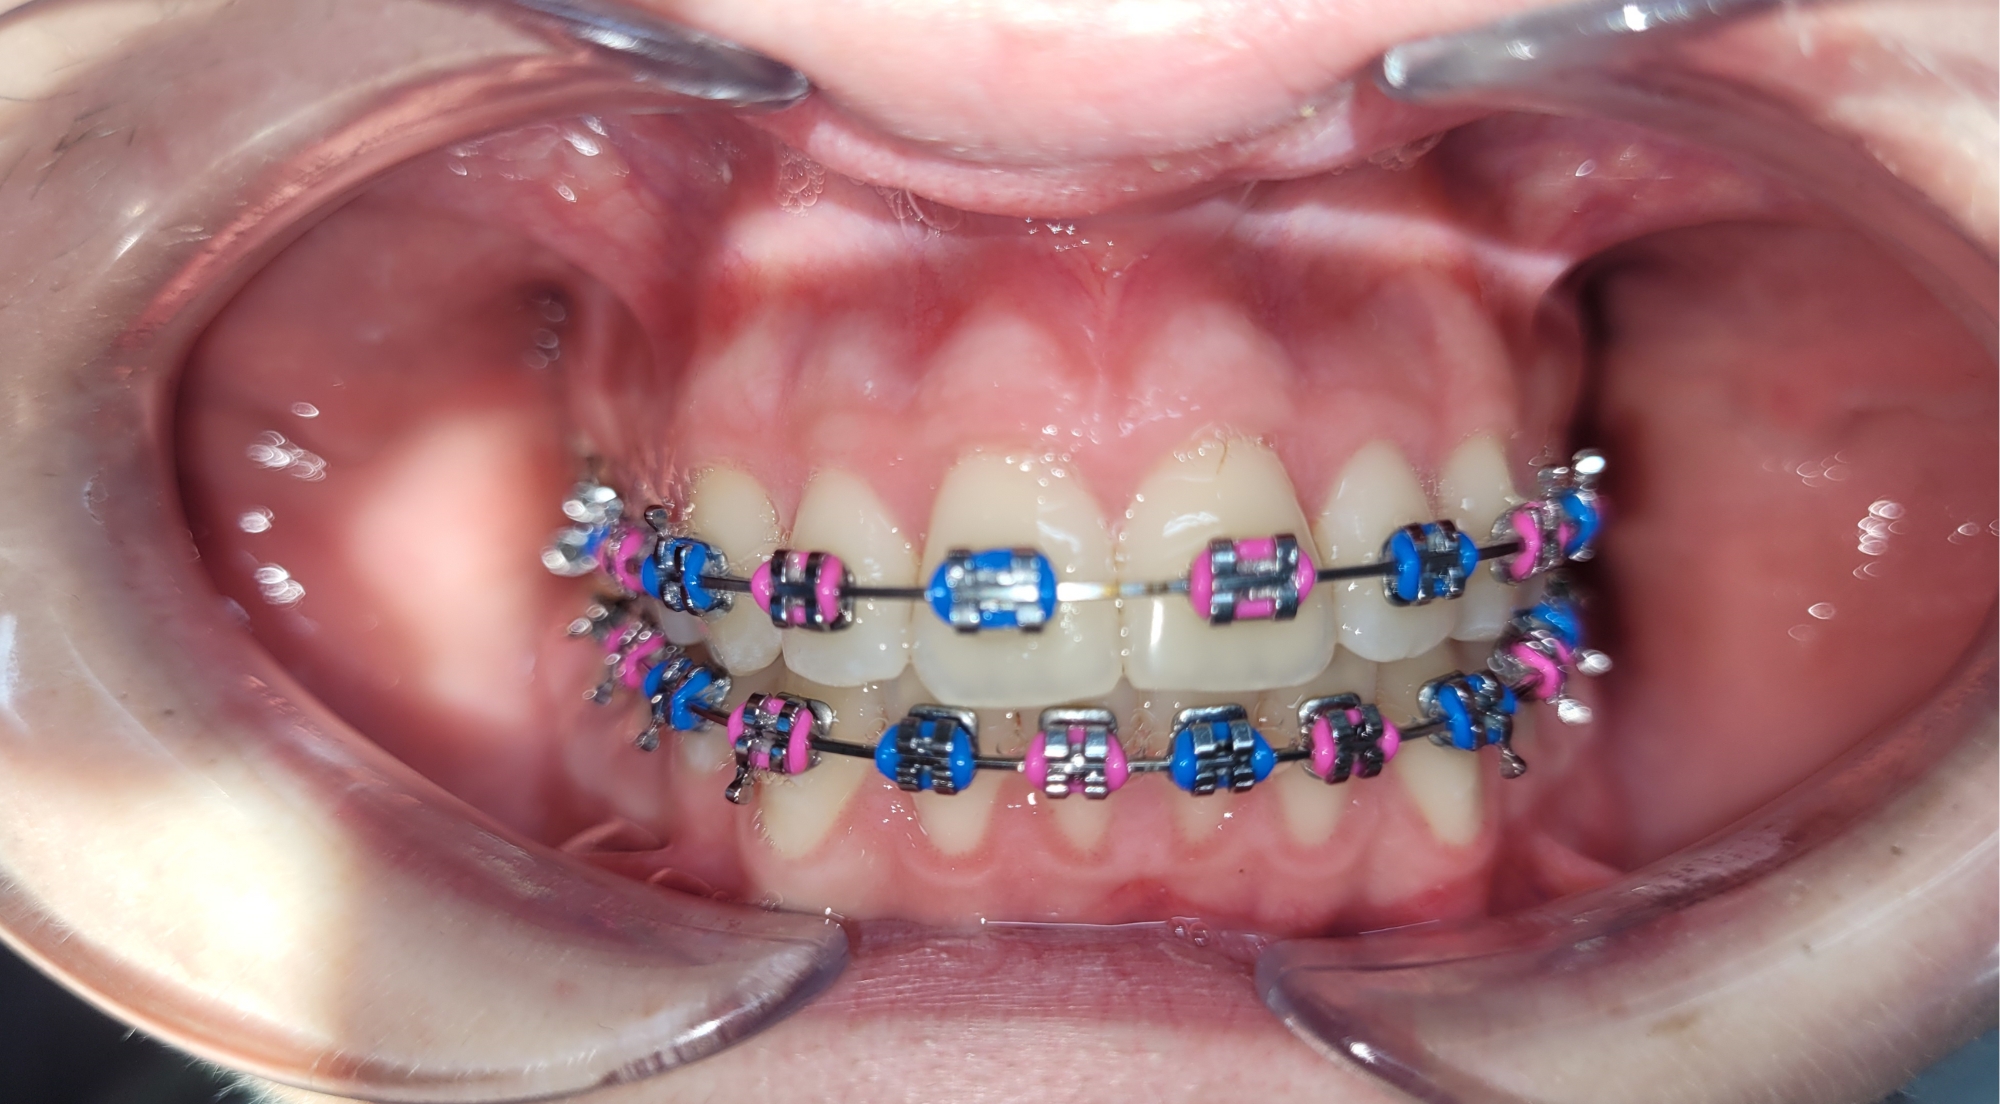

Po przeprowadzeniu kompleksowej diagnostyki, obejmującej m.in. analizę cefalometryczną, analizę zdjęcia panoramicznego i modeli diagnostycznych, zdecydowaliśmy o wdrożeniu leczenia aparatem stałym przedsionkowym w obu łukach zębowych.

Dzięki konsekwentnemu przestrzeganiu zaleceń i regularnym wizytom kontrolnym leczenie przebiega zgodnie z planem. Obecnie jesteśmy na końcowym etapie terapii – przed zdjęciem aparatu. Osiągnięto już znaczącą poprawę pozycji zębów oraz korektę zgryzu krzyżowego.

Finishing czyli końcowa faza leczenia ortodontycznego ma na celu uzyskanie prawidłowych kontaktów zębowych i zapewnienie stabilności efektów leczenia w przyszłości. Już teraz widać wyraźną różnicę – zęby są wyrównane, a łuki zębowe harmonijne i symetryczne.